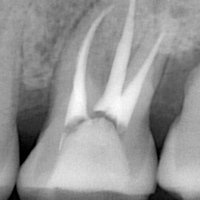

むし歯菌に侵された歯の根管という部分の治療を行います。感染部分の除去や洗浄・消毒など、丁寧な治療が必要になるため時間がかかりますが、歯を長く残すための重要な治療です。